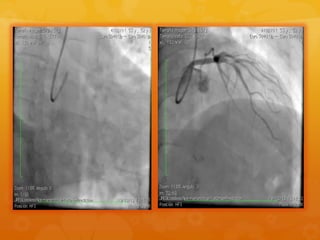

STENT EN CD PATENTE

STENT EN CDPATENTE